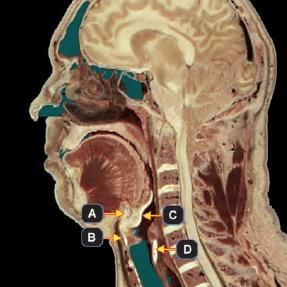

A newborn baby has presented with a pharyngeal pouch developmental anomaly. Facial twitching observed is due to involvement of which of the following marked region? (INI-CET July 2021)

Detailed Solution for Test: Anatomy - 3 - Question 9

The infant seems to have DiGeorge syndrome, which may arise from irregular development of the third and fourth pharyngeal pouches. The accompanying facial twitching, triggered by the Chvostek sign, could be a result of hypocalcaemia due to the abnormal formation of the inferior parathyroid gland (Marker B).

• It is important to note that while DiGeorge syndrome involves both pharyngeal pouches 3 and 4, pouch 3 is referenced more frequently, as the thymus originates from it. Thymic aplasia is a characteristic feature of the syndrome.

• Marker A: Pharyngeal pouch 2 (Derivative: Tonsillar epithelium).

• Marker C: Pharyngeal pouch 3; Ventral portion (Derivative: cytoreticular cells of Thymus).

• Marker D: Pharyngeal pouch 4; Derivative: Superior parathyroid.

DiGeorge syndrome results from abnormal migration of neural crest cells and is characterised by hypoparathyroidism, the absence of the thymus gland (leading to T-cell abnormalities), and cardiac anomalies involving the aorta and pulmonary septum.